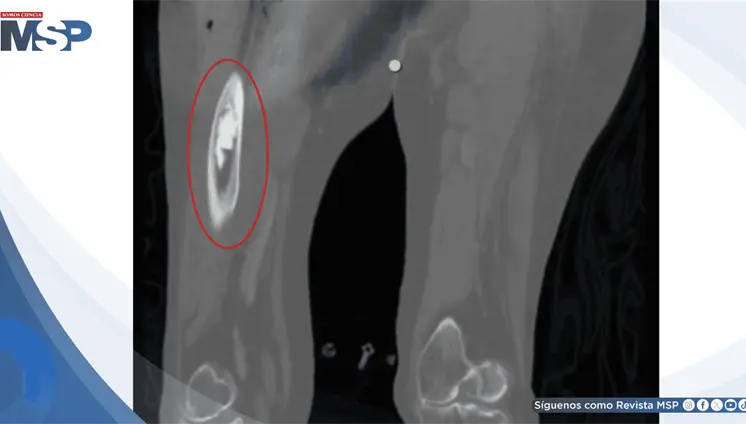

Masa de más de 15 cm secundaria a desgaste de prótesis metal-metal implantada 27 años atrás simuló cáncer

Enero 12, 2026